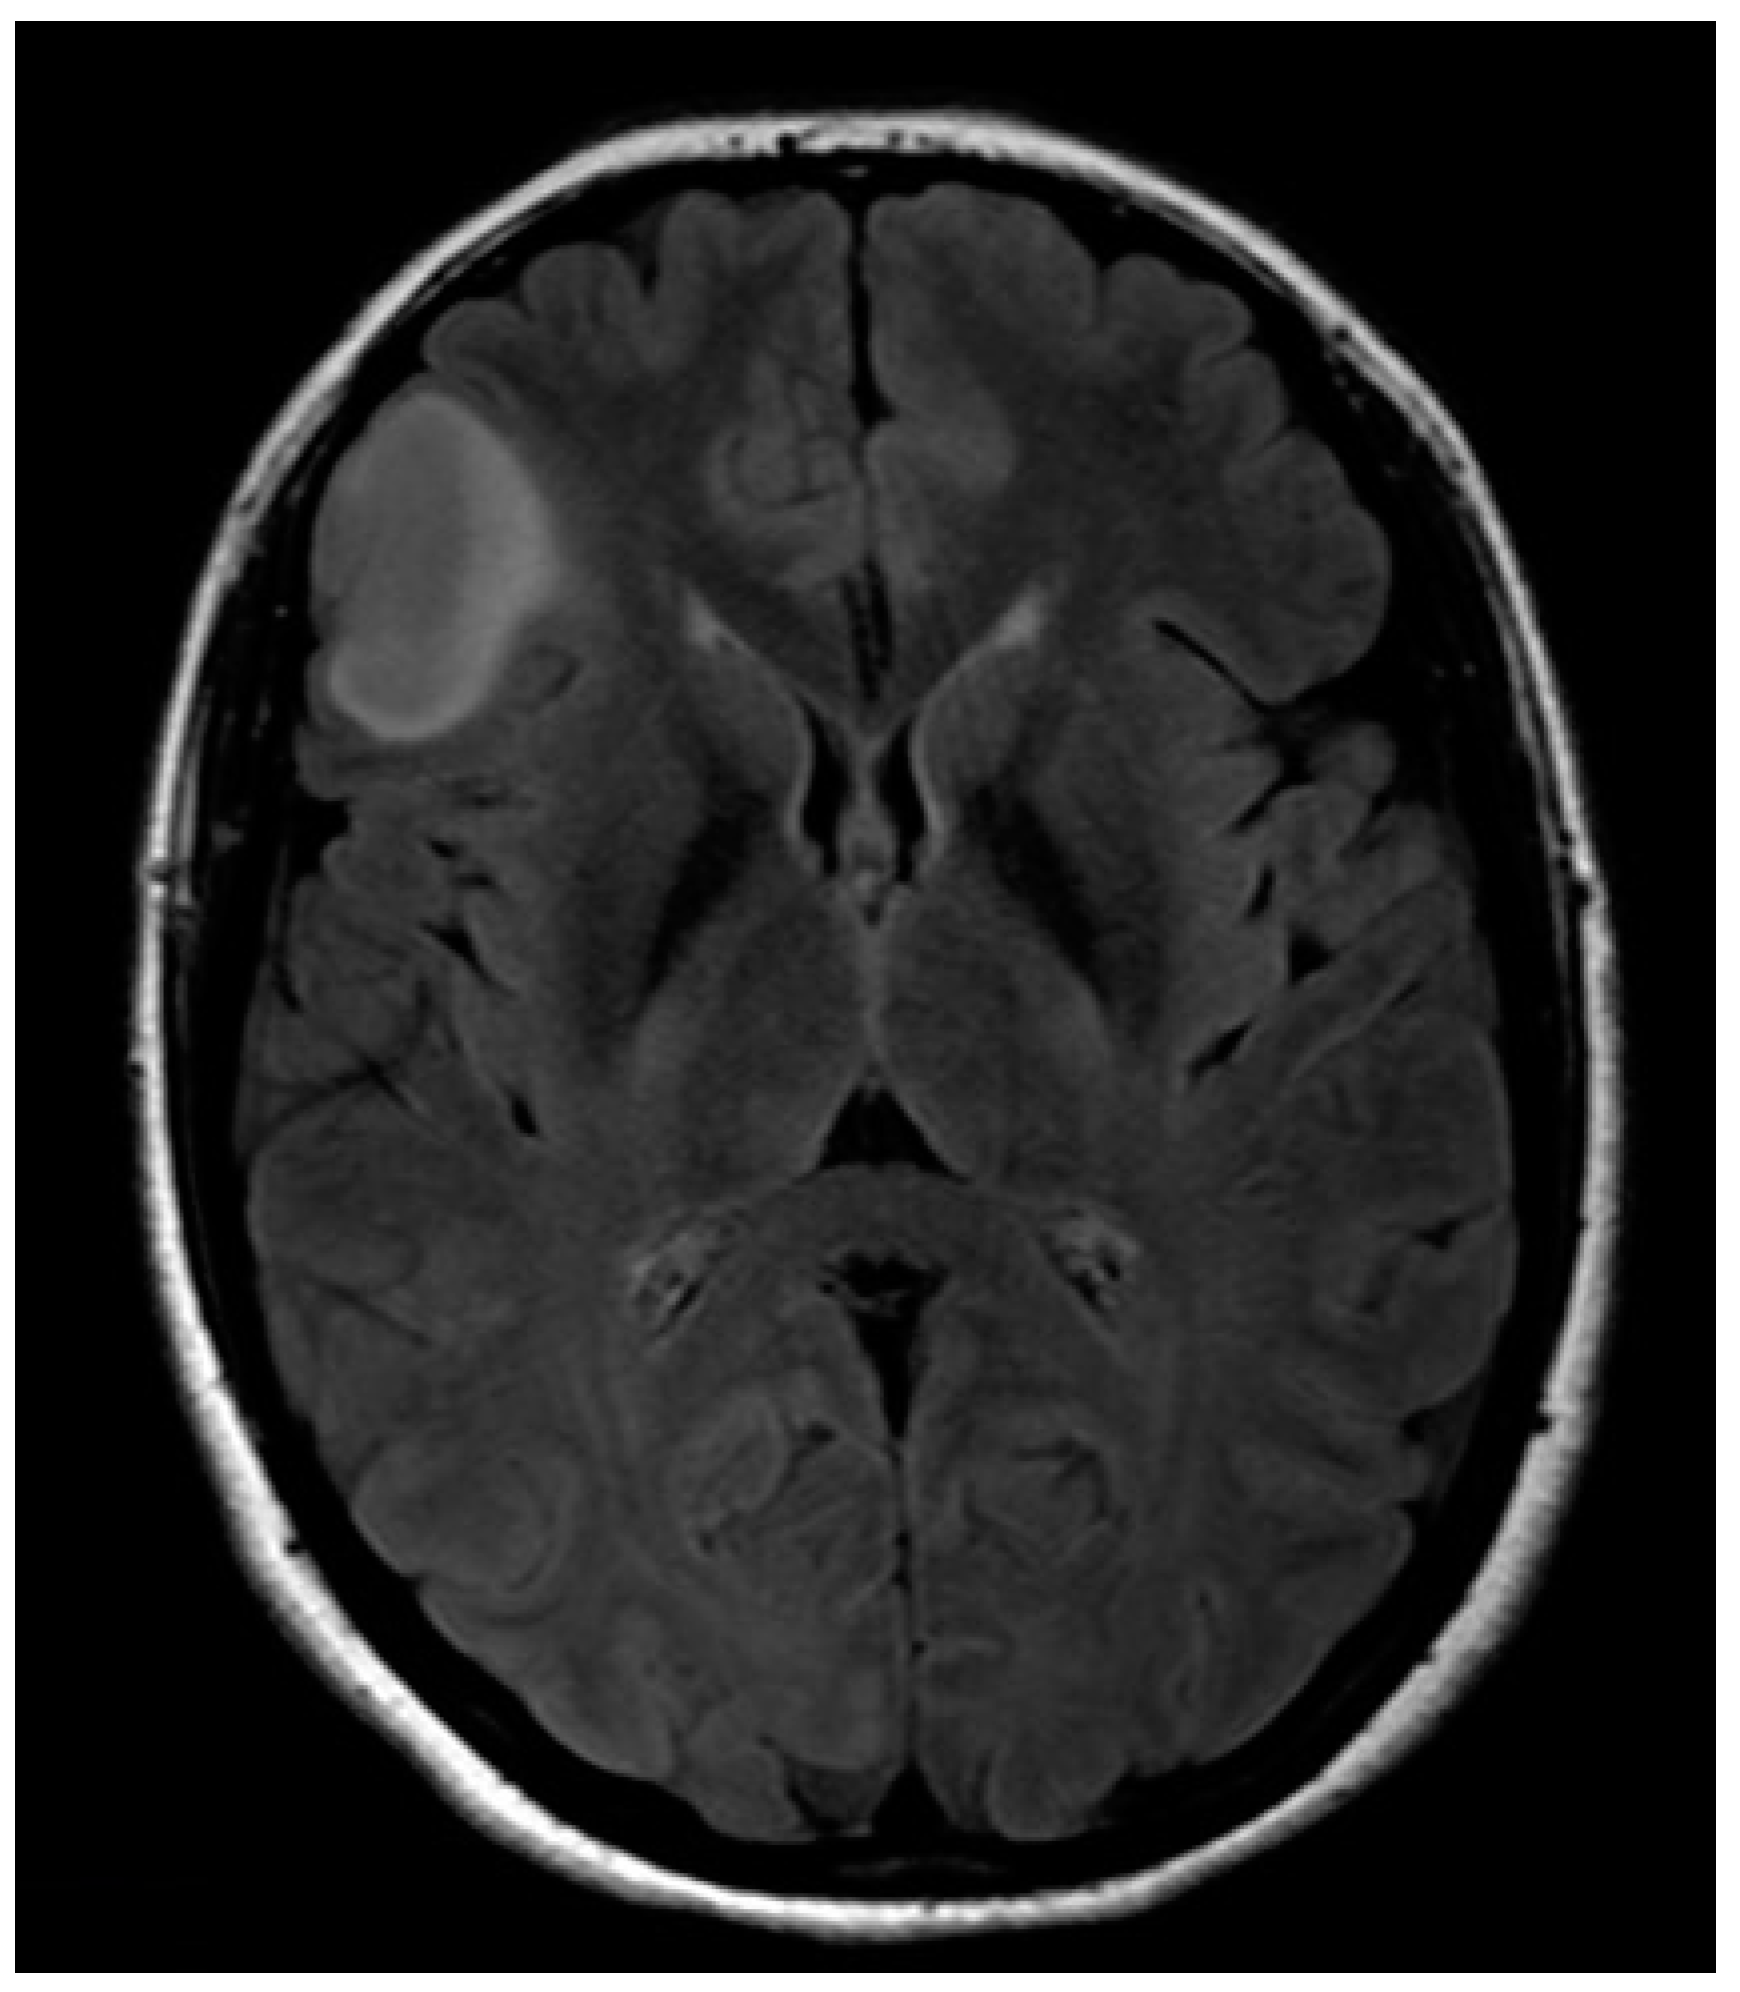

Histology provided evidence for isocitrate dehydrogenase 1(IDH1)-mutated, ATP-Dependent Helicase (ATRX)-wild diffuse low-grade astrocytoma. Postoperative MR showed a subtotal removal with residual disease where IFOF was intraoperatively identified (Figure 5). No adjuvant therapy was then proposed, and the patient is currently fully working. If evidence of residual disease progression is observed, a new surgery will be proposed, delaying eventual adjuvant therapy as much as possible.

Figure 5. Post-operative anatomical MRI.

Brainsci 08 00192 g005